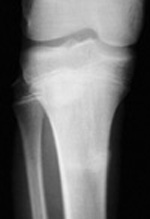

Can you name the fractures below? Click on the button for answers. | ||||||

| AP and lateral knee views of a subtle fracture. | ||||||